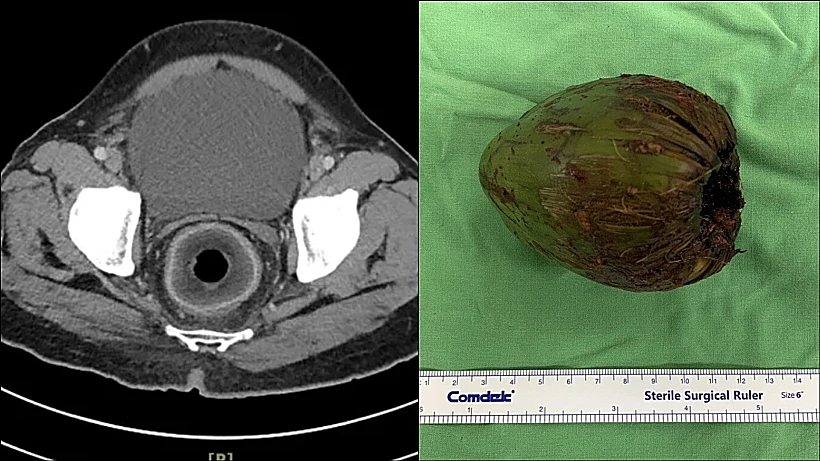

מוקדם יותר השנה פורסם מקרה אודות גבר בן 56 מקאושיונג, טייוואן, שהגיע לבית החולים לאחר שנתקע לו אגוז קוקוס בפי הטבעת. הקוקוס דחס את השופכה הערמונית של הגבר, מה שגרם לו לאצירת שתן.

הרופאים ניתחו את האיש והסירו אגוז קוקוס באורך 7.5 ס״מ וברוחב 5.7 ס״מ. בדו״ח הרפואי שפורסם בכתב העת המדעי The British Journal of Surgery צוין כי האיש סירב לענות על שאלות הרופאים ואמר רק מילה אחת: ״קוקוס״.